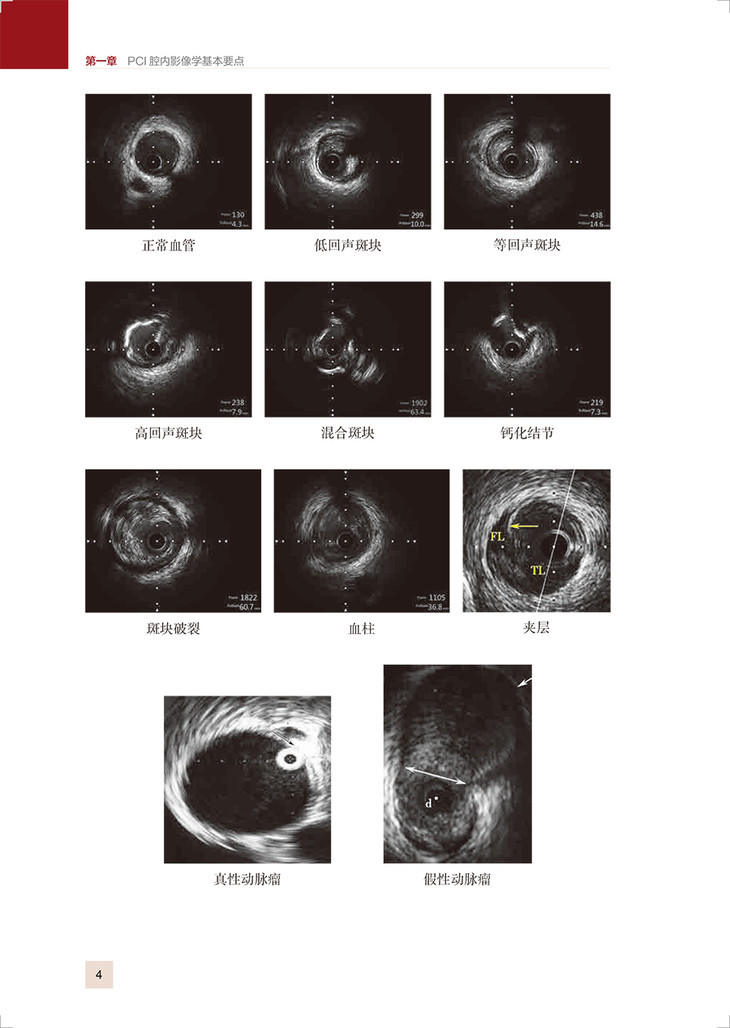

第一章 PCI 腔内影像学基本要点/1

一、 IVUS 原理、测量方法及识图/2